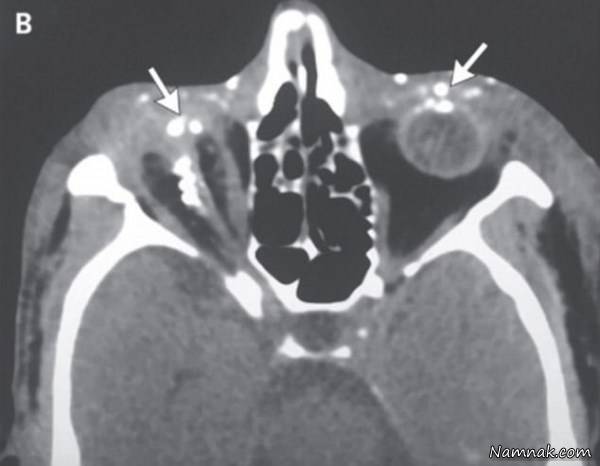

دیلی میل تصاویر دلخراشی از نابینا شدن مردی که بر اثر برخورد مواد منفجره به صورتش دچار حادثه شد را منتشر کرد تا هشدار دهنده بودن این نوع تفریحات را به تصویر بکشد.مردی 44 ساله اهل هند که نامش منتشر نشده است بر اثر برخورد ذرات مواد منفجره به صورتش بینایی کامل یکی از چشمان خود را از دست داد.

آسیب شدید ناشی از پرتاب ذرات ریز مواد منفجره توانایی چشم راست او را به طور کامل از بین برد از طرفی بعد از حادثه به سرعت به بیمارستان منتقل نشده و تاخیر در درمان منجربه کوری یکی از چشمانش شد.

پزشک معالج تمام سعی خود را به کار گرفت تا در نهایت بینایی چشم چپ او را حفظ کند. دکتر " جاگات رام" پزشک معالج این مرد گفت:پرتاب ذرات ریز و داغ از ماده منفجره که به دلیل سرعت بالا قدرت بیشتری گرفته بود آسیب جدی به چشمان بیمار وارد ساخته بود به طوری که حتی جدا کردن و رفع اثرات این ذرات از روی چشم نابینا شده مرد ناممکن بود ، از بین رفتن لایه ای از قرنیه به واسطه برخورد شدید ذرات مواد منفجره کاردرمان را دشوار می کرد.برای همین درمان اصلی مان را روی درمان چشم چپ بیمار متمرکز کردیم تا حد ممکن بینایی آن را حذف کنیم.